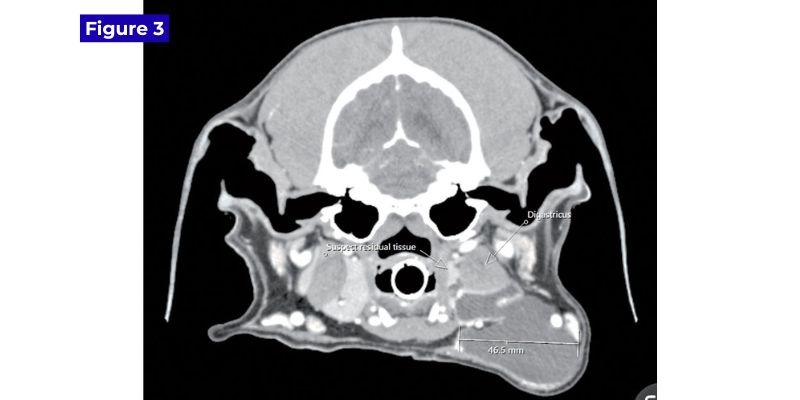

At Tully's two-week healing recheck, no evidence of sialocele recurrence was seen, but four months later, a fluctuant left neck swelling recurred. A conventional CT scan was recommended. The conventional CT scan was done at Ryan Veterinary Hospital at the University of Pennsylvania, which ensured saliva was not arising from another salivary gland, such as the parotid or zygomatic gland. CT also identified a possible remnant of sublingual salivary gland, which was approximately 9 mm wide (Figure 3).

Axial image from a conventional CT scan with contrast, showing a possible salivary

remnant medial to the digastricus and ventral to the carotid artery. Photo courtesy Dr. John R. Lewis